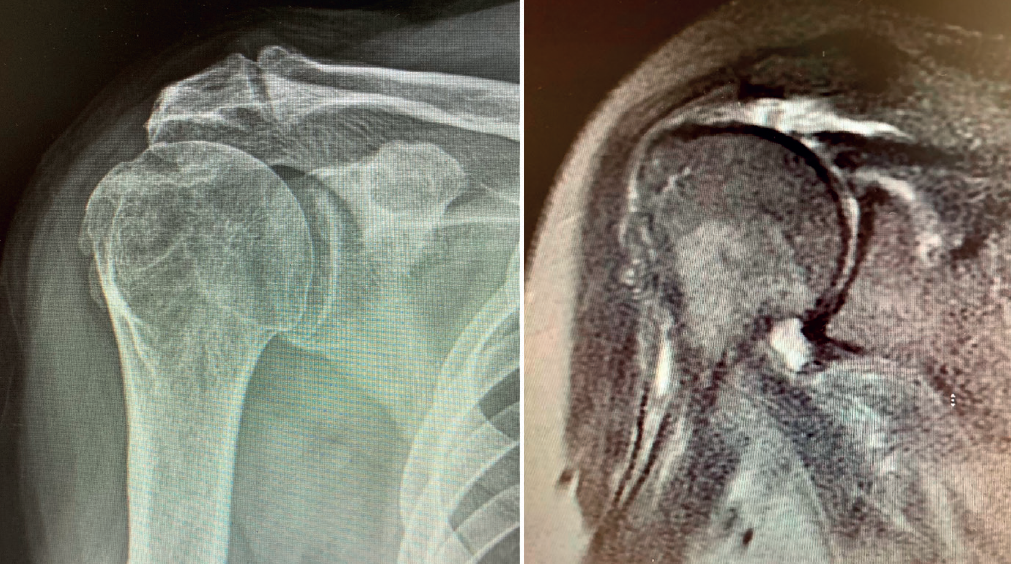

A more controversial issue is its indication in patients with massive cuff rupture in the absence of arthropathy, since it implies performing joint replacement of a joint without osteoarthrosis. In these cases, reverse shoulder replacement has been shown to be an effective alternative that affords predictable pain relief and improved function(15,17)(Figures 1 to 5).

Reverse shoulder replacement shifts the center of rotation distal and medial (Figure 5), increasing the lever arm of the deltoid muscle and recruiting more anterior and posterior fibers of the muscle, improving its function in patients without rotator cuff(1,19,20). In general, the patients can be expected to show increased anterior flexion and abduction of the shoulder. Having greater or lesser external rotation will depend on the quality of the teres minor and infraspinatus, among other factors (Figure 4). With regard to internal rotation in patients with reverse shoulder replacement after massive rupture, the results are less predictable and are conditioned by the implant design and the characteristics of the patient, among other factors. We must know the functional limitations of the implant and inform our patients about the results that can be expected.